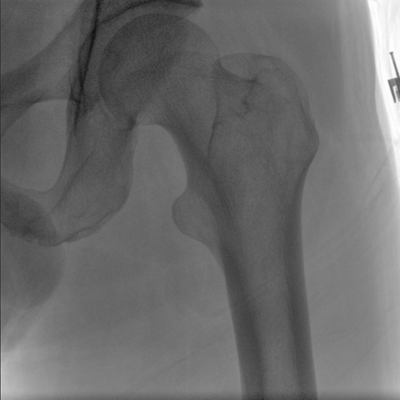

大尺寸動態(tài)平板探測器,高DQE、低噪聲、圖像清晰。采用多分辨率圖像增強(qiáng)處理技術(shù),不同部位不同圖像處理算法,滿足客戶多樣化的需求。

采用智能變頻脈沖透視技術(shù),優(yōu)化圖像質(zhì)量的同時降低輻射劑量,呵護(hù)醫(yī)患健康